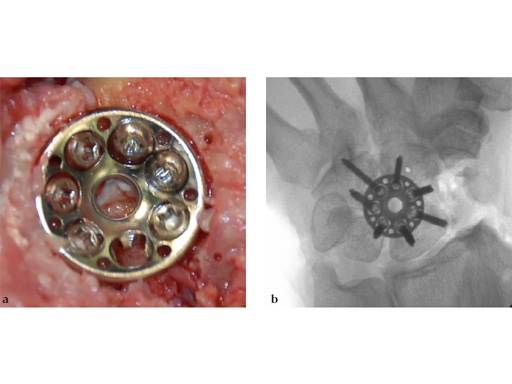

Fig 1: VA Locking Intercarpal Fusion Plate

The 2.4 mm VA-locking intercarpal fusion system combines a circular plating technique with 2.4 mm variable angle locking technology and dedicated instrumentation . The circular plate design with a smooth surface and rounded edges minimizes soft-tissue irritation (Fig 2). To avoid impingement, proper positioning of the fusion as well as accurate placement and recession of the implant is mandatory. In addition to the standard reaming guide (Fig 3 in Instrument tab), the new reduction reaming guide permits reduction, compression and stabilization of the fusion site during the reaming procedure (Fig 4 in Instrument tab). Laser markings on the reamer support the surgeon by precisely controlling the depth of reaming for optimal countersinking of the plate (Fig 5 in Instrument tab).

The available two plate sizes include a 6-hole plate with a diameter of 15 mm, and a 7-hole plate with a diameter of 17 mm to fit different sized patients and applications.